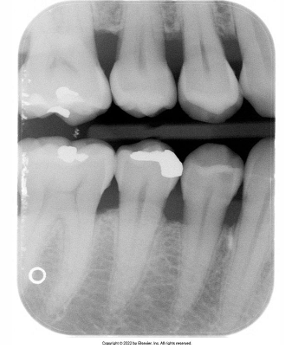

What is the problem with this Overlapped contacts X-ray?

Central ray not directed through the interproximal spaces

How would you resolve this Overlapped contacts X-ray?

Direct the x-ray beam through the contacts